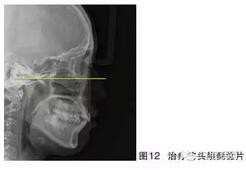

患者女,24歲,主訴“牙齒不齊”?;颊呙嫦窦翱趦?nèi)像如圖10~11所示,頭顱側(cè)位片如圖12所示。臨床檢查可見(jiàn):上下頜中度擁擠,上頜尖牙頰向遠(yuǎn)中錯(cuò)位,磨牙關(guān)系Ⅰ類(lèi)尖窩關(guān)系,前牙輕度唇傾,口外觀(guān)、換成嘴唇輕微前突。診斷:牙列擁擠伴輕度齒槽性前突。